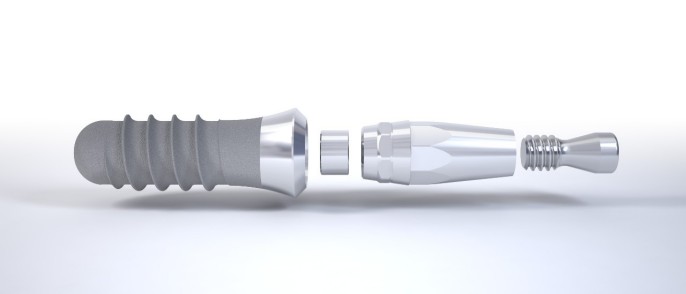

¿Qué es un implante?

Los implantes dentales son dispositivos que, insertados en el hueso, funcionan o actúan como una raíz artificial, soportando así la futura corona protética por medio de un aditamento intermedio conocido como pilar.

Los implantes como medio para una prótesis

Una vez respetado el período de cicatrización, se llevará a cabo la restauración protética, esto es, conectar el implante osteointegrado a una corona a través de un elemento intermedio conocido como pilar. Este procedimiento puede realizarse de manera atornillada o cementada.

Coronas atornilladas. La fijación de la corona al pilar se lleva a cabo por medio de un tornillo que la atraviesa. El orificio de conexión o “chimenea” será ocultado posteriormente con composite. Importante destacar el riesgo estético inherente asociado a este procedimiento ante la posibilidad de diferencia cromática entre el composite que obtura la chimenea y la cerámica de la corona.

Coronas cementadas. Estéticamente más favorables, la unión de la corona al pilar se realiza por medio de un agente cementante. El riesgo asociado a este procedimiento radica en la dificultad de remoción de los posibles excesos de cemento que pueden causar irritación de los tejidos.